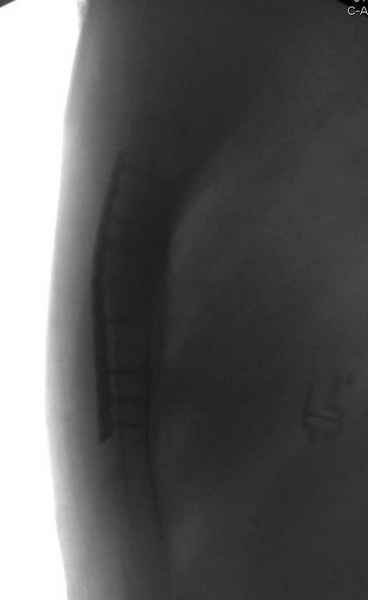

Юра, интересно, насколько такой остеосинтез контролирует степень репозиции, а то у меня имеются снимки девочки 11 лет, направленной ко мне на консультацию из одной из республик бывшего союза.

После торакальной операции, по-видимому, сильно натянули проволоку, и в результате получился захлест отломков в друг друга.